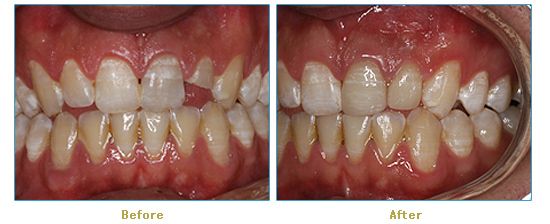

Dr. Cabianca has restored hundreds of smiles through the latest techniques in restorative and cosmetic dentistry. The following before and after photos document a few such cases in which Dr. Cabianca has replaced and reshaped teeth to produce wonderful smiles. Click on any of the images below to view larger versions of the photos.